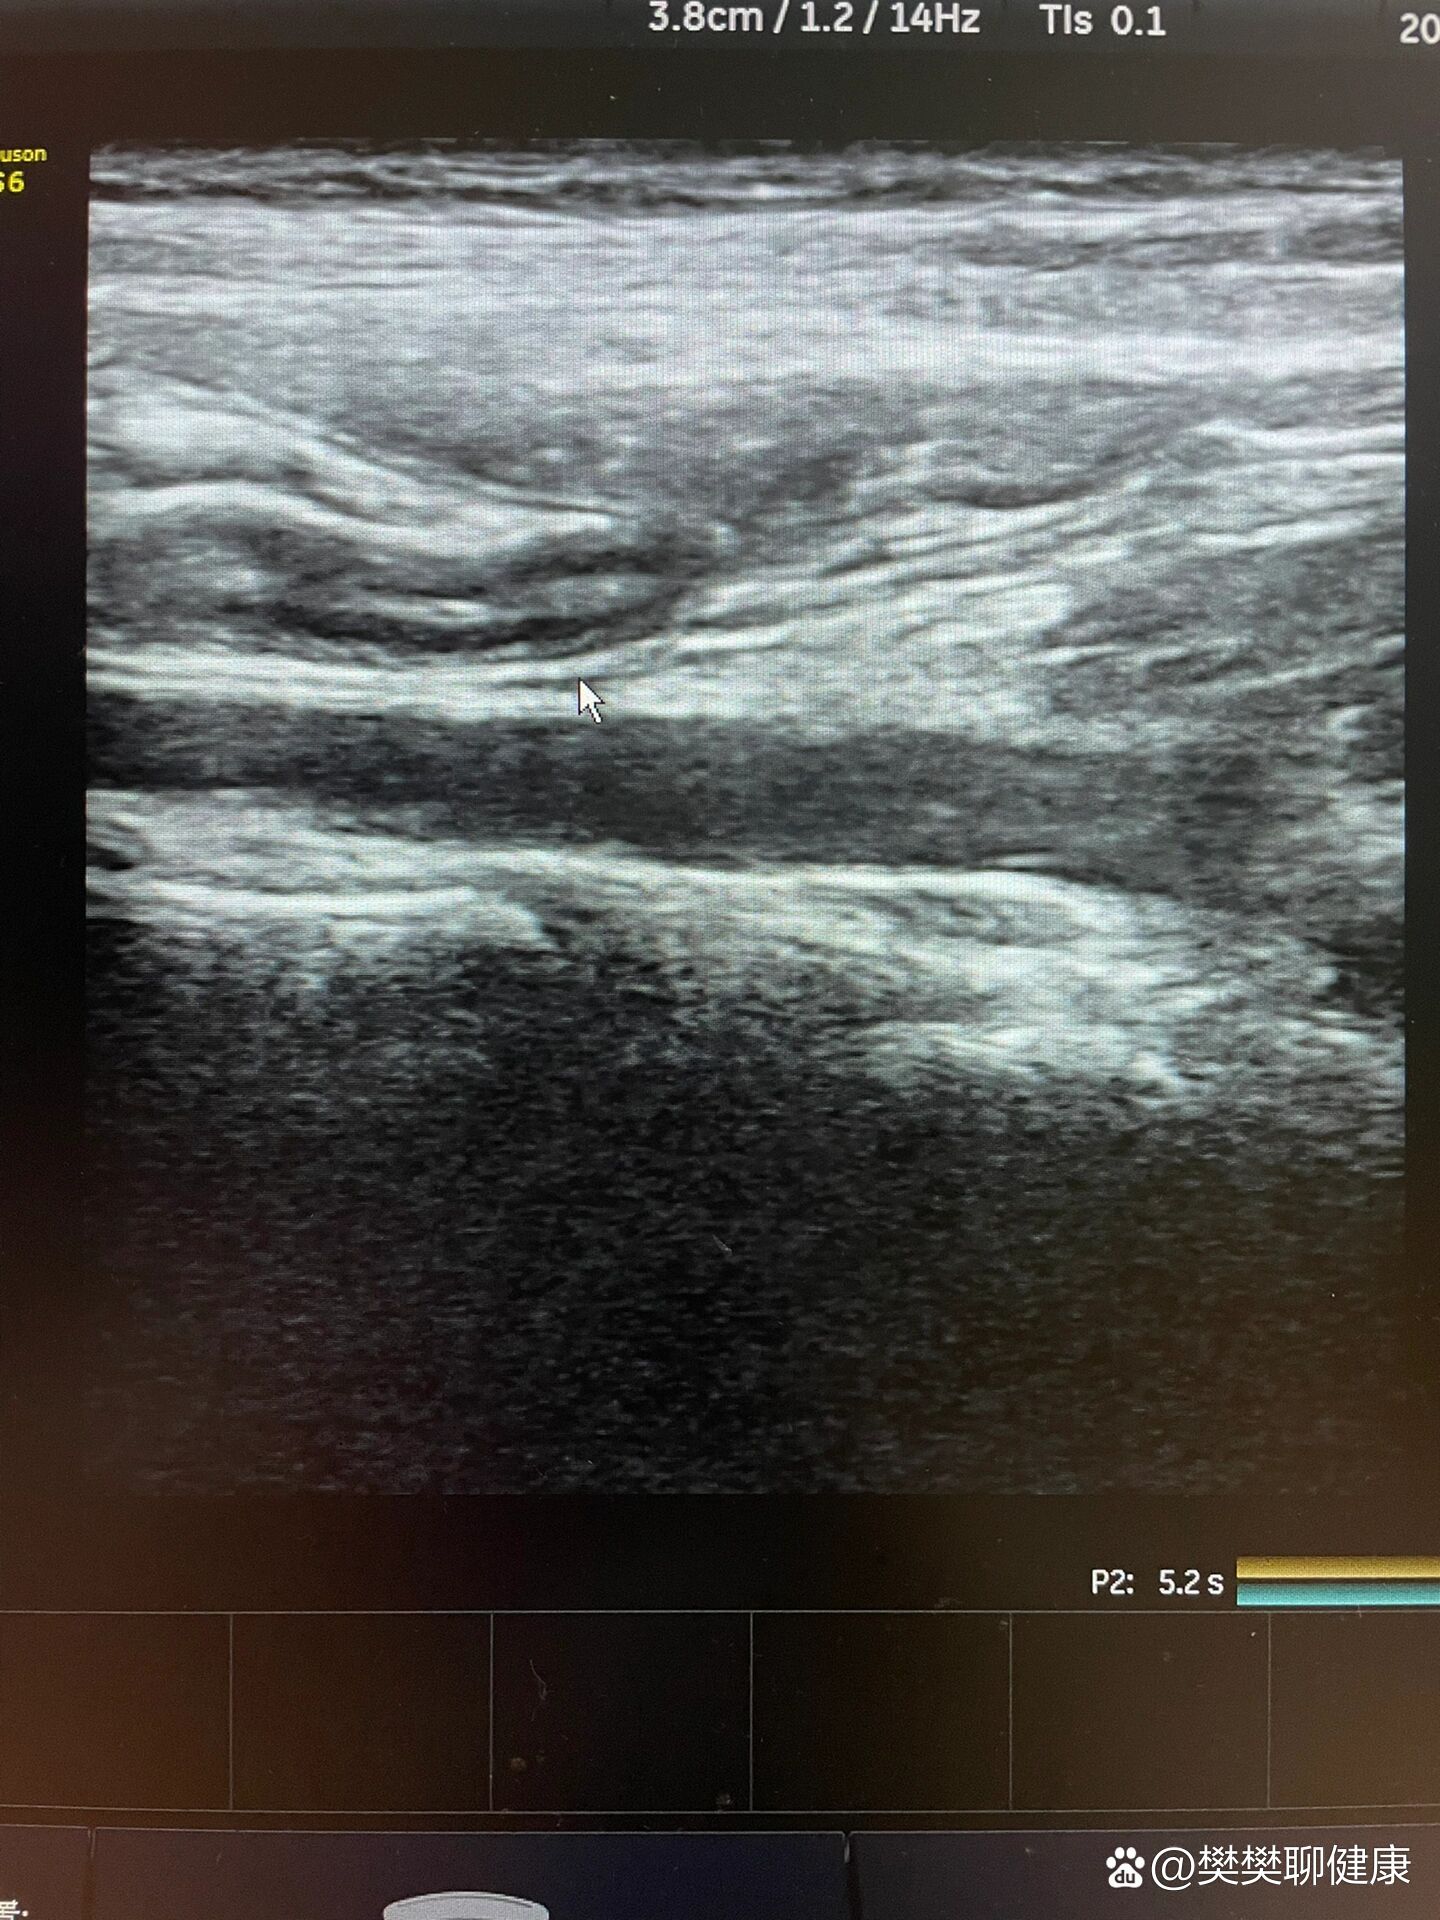

小孩阑尾炎超声诊断的挑战与影像分析

图片尺寸614x709